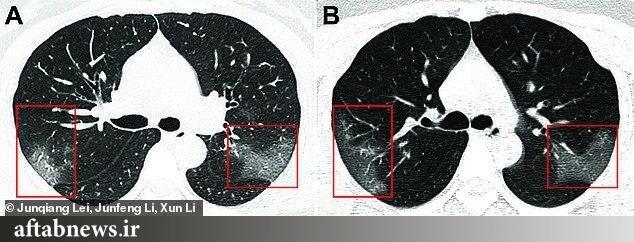

سرویس سلامت- تصاویر گرفته شده با اشعه ایکس نشان میدهند ویروس مرگبار کرونا تا چه اندازه بر روی اندامهای حیاتی فرد مبتلای ۳۳ ساله تاثیر گذاشتهاند.

به گزارش آفتابنیوز؛ این تصاویر متعلق به زنی ۳۳ ساله و بستری شده در بیمارستان لانژو در چین است که پیش از انتقال به بیمارستان در ووهان به ویروس کرونا مبتلا شده بود.

درجه دمای بدن او ۱۰۲ فارنهایت یا ۳۹ درجه سانتیگراد ثبت شده است. علائم آشکار شده بر روی ریه فرد به صورت تکههای سفید رنگ قابل مشاهده هستند.